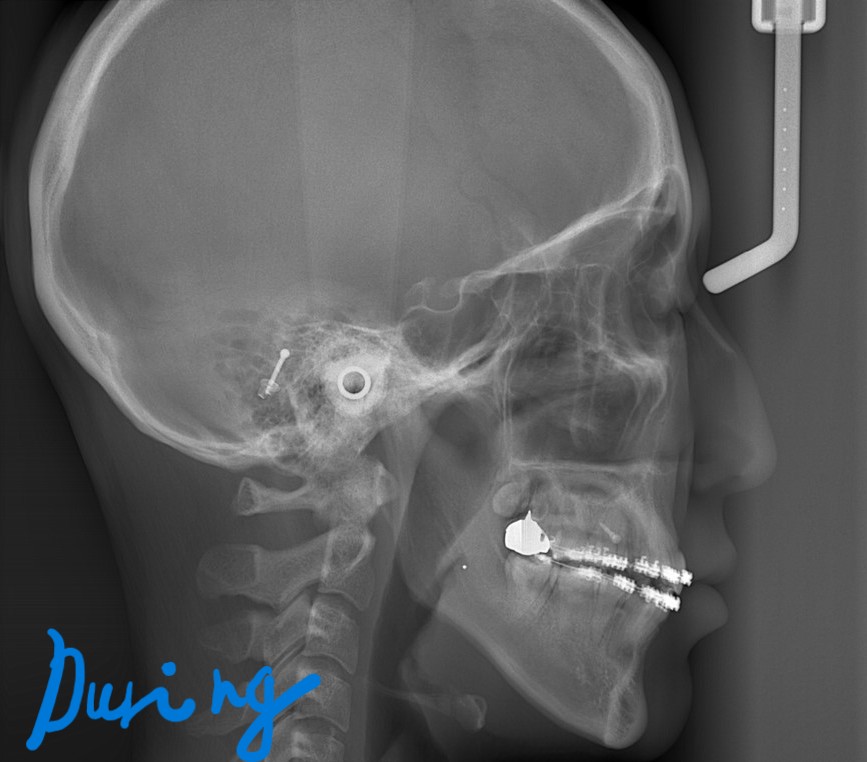

【途中経過】 当初に抜歯をして出来たスペース分は、しっかりと引っ込めることが出来ました。

現状としては、ここまで口元が引っ込みました。

最初と比べてみると、

患者さんとも話して、「再び4本抜歯は嫌だけど、もうちょっとでも引っ込められるなら、頑張りたい!」という希望でした。

そこで、アンカースクリューを追加して歯列ごと更に引っ込めることにしました。